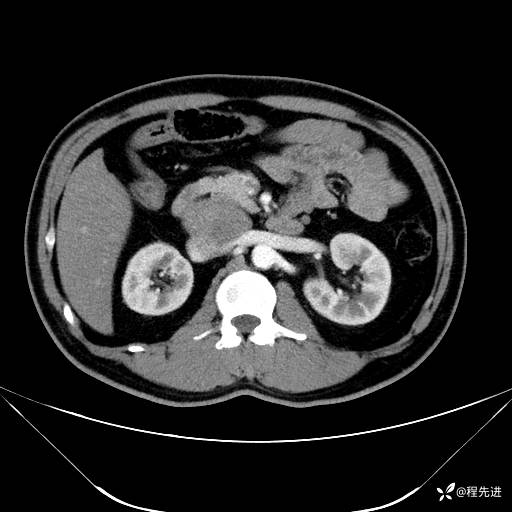

【腹盆】特别精彩病例|发现腹膜后肿物1月余

主诉:发现腹膜后肿物1月余

现病史:患者1月余前查体,行超声检查提示:后腹膜囊实性肿块;慢性胆囊炎伴胆囊内结石;无腹痛腹胀,不伴腹泻发热等;偶感腰背部酸痛。

CT平扫+增强: